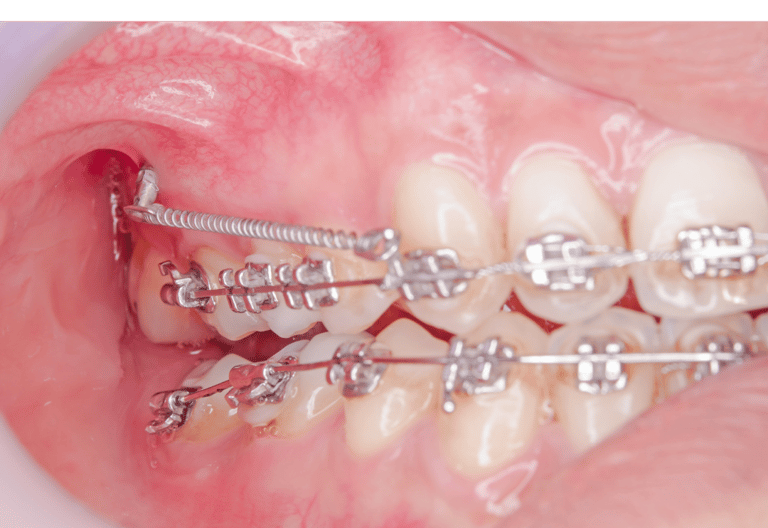

Mikroimplanty ortodontyczne – małe, biokompatybilne śruby, które stają się Twoimi niewidocznymi sprzymierzeńcami w dążeniu do perfekcyjnego uśmiechu!

Mikroimplanty zapewniają stabilne punkty zaczepienia dla sił ortodontycznych, umożliwiając precyzyjne i kontrolowane przesuwanie nawet najbardziej opornych zębów.

Mikroimplanty otwierają nowe możliwości leczenia nawet skomplikowanych wad zgryzu, które wcześniej mogły wydawać się trudne do skorygowania.